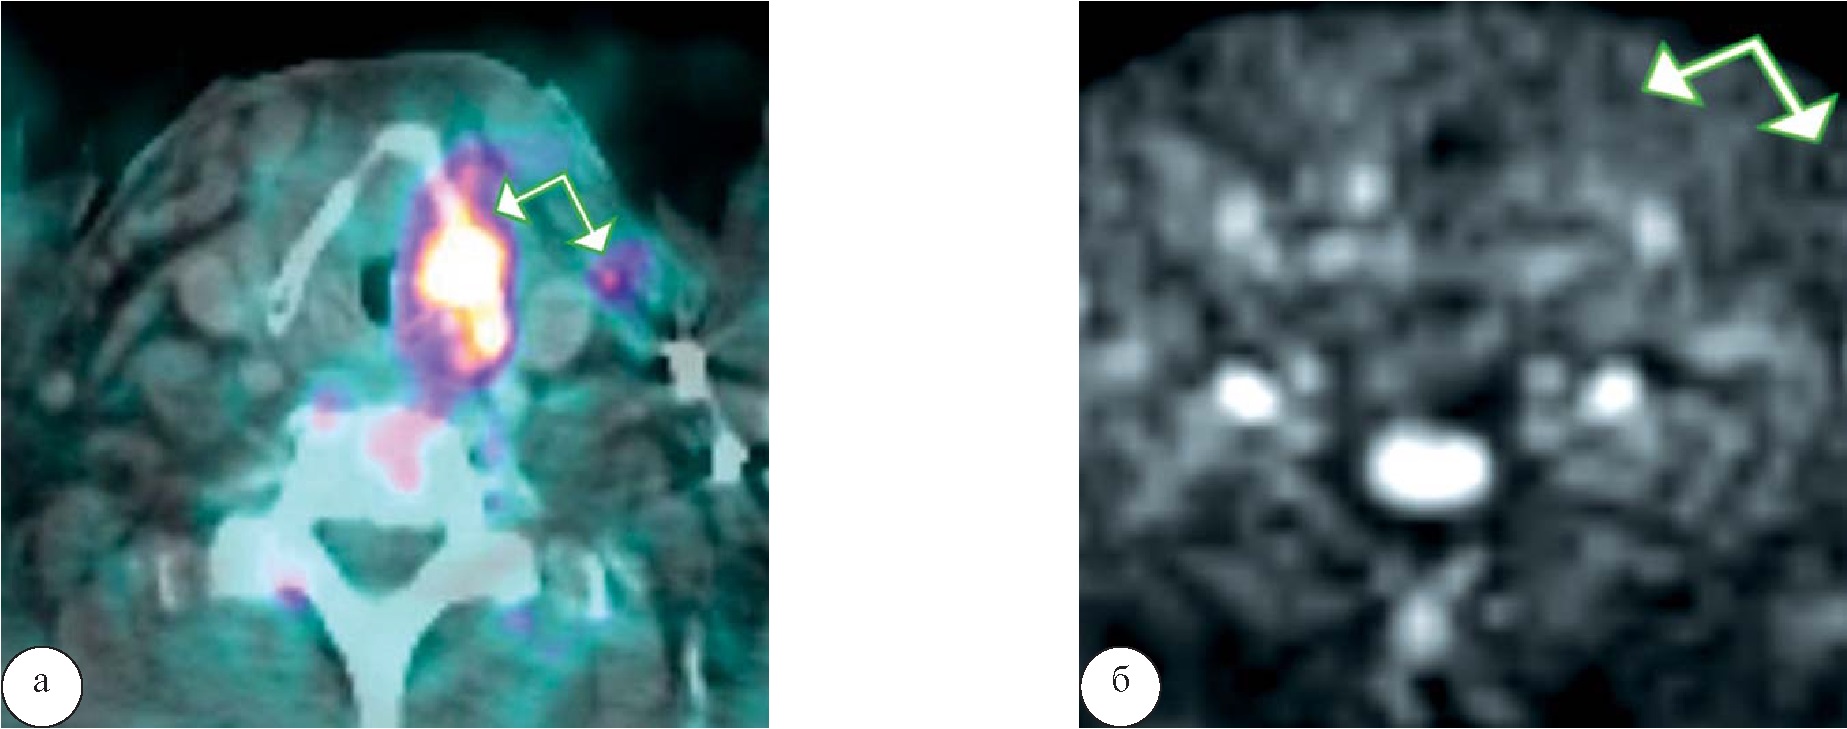

В первой группе у 1 (1,8%) человека в области образования левой голосовой складки, характеризующегося отсутствием гиперинтенсивного сигнала на ДВИ, отмечался гиперметаболизм 18-ФДГ (SUVmax 12,3), а также единичные вторично измененные шейные лимфатические узлы слева с гиперфиксацией РФП в них (SUVmax 8,9), рисунок 4.

Рис. 4. Высокодифференцированный рак гортани с метастазированием в регионарные лимфатические узлы. При ПЭТ/КТ (а) определяется образование в области левой голосовой складки и лимфатический узел III группы слева с повышенным уровнем метаболизма 18-ФДГ, однако при МРТ на ДВИ (б) повышения сигнала в области образования и в области лимфатического узла не отмечается